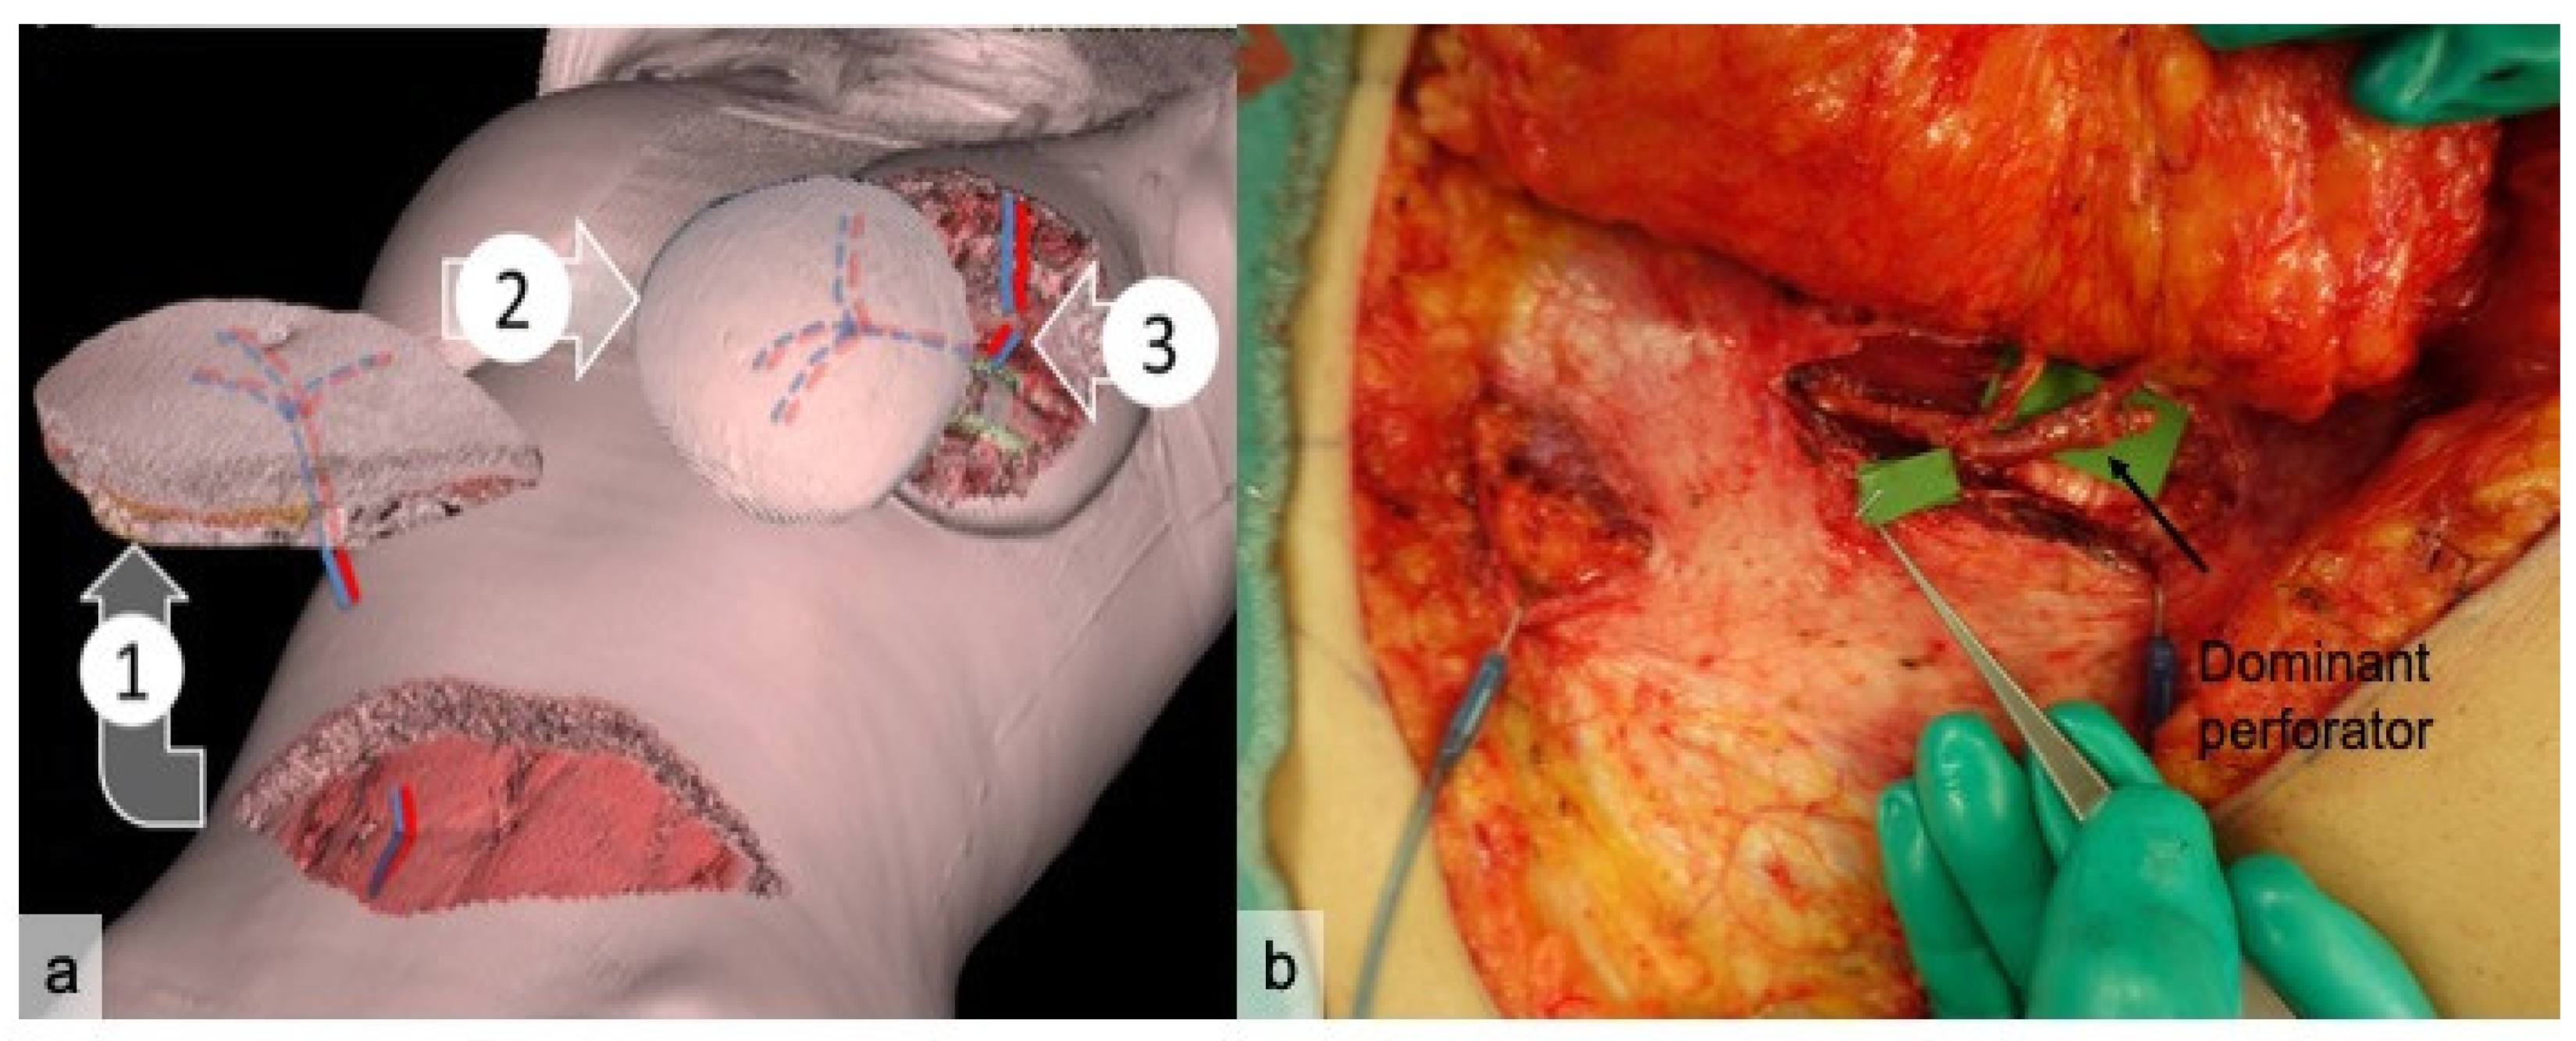

2. Materials and Methods

3. Results

4. Discussion